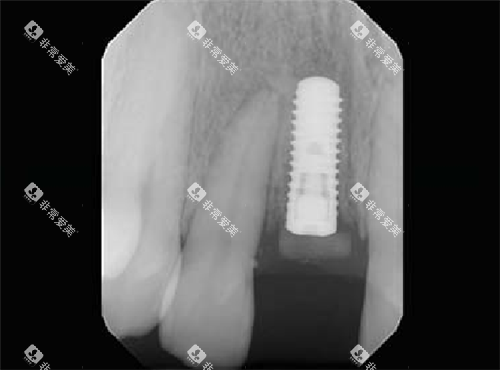

瑞士士卓曼iti种植牙植入后